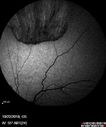

Familial Exudative Vitreoretinopathy - FEVR - Stage 4b OD384 views10 year old child with poor vision OD from birth. The left eye had vascular remodelling in the temporal periphery with preretinal abnormalitlies seen on OCT. The patient never returned for a fluorescein angiogram. Left eye is either stage 1 or stage 2. no family historyJan 01, 2019

Familial Exudative Vitreoretinopathy - FEVR - Stage 4b OD582 views10 year old child with poor vision OD from birth. The left eye had vascular remodelling in the temporal periphery with preretinal abnormalitlies seen on OCT. The patient never returned for a fluorescein angiogram. Left eye is either stage 1 or stage 2. no family historyJan 01, 2019